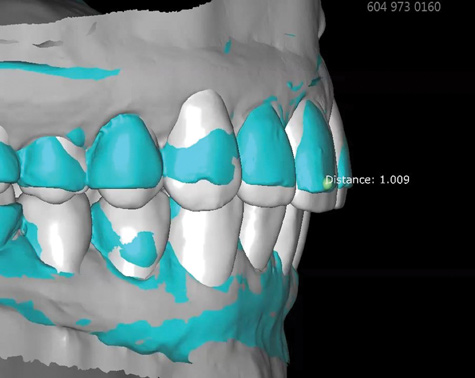

Fig 8. Scans used to mock-up desired restorative result using modeling software. The teal-green areas represent the current tooth form, and the white areas show the desired or digital wax-up. A reduction of 1.009 mm was required prior to preparation, making endodontic treatment likely if orthodontic treatment is not considered.

Figure 8

Fig 9. Scans used to mock-up desired restorative result using modeling software. The teal-green areas represent the current tooth form, and the white areas show the desired or digital wax-up. A reduction of 1.009 mm was required prior to preparation, making endodontic treatment likely if orthodontic treatment is not considered.

Figure 9

3. The face scan coupled with an optical scan or scanned impressions/casts, which are used to mock-up the desired restorative result by using a modeling software. This allows for creation of digital wax-ups and restoration designs, comparison of pre/post-restoration contours and positions using transparent overlays (permitting viewing of the anticipated changes relative to baseline through the use of 3D superimposition), and anticipation of endodontic procedures that may be required due to the expected reduction of tooth structure needed to achieve the desired outcome without altering tooth positions (Figure 8 and Figure 9). In turn, multiple try-ins and adjustments resulting from insufficient information are either entirely avoided or minimized. This detailed information is almost impossible to visualize using stone models. Also, it reduces working time in the design phase and "virtually" archives all proposals.